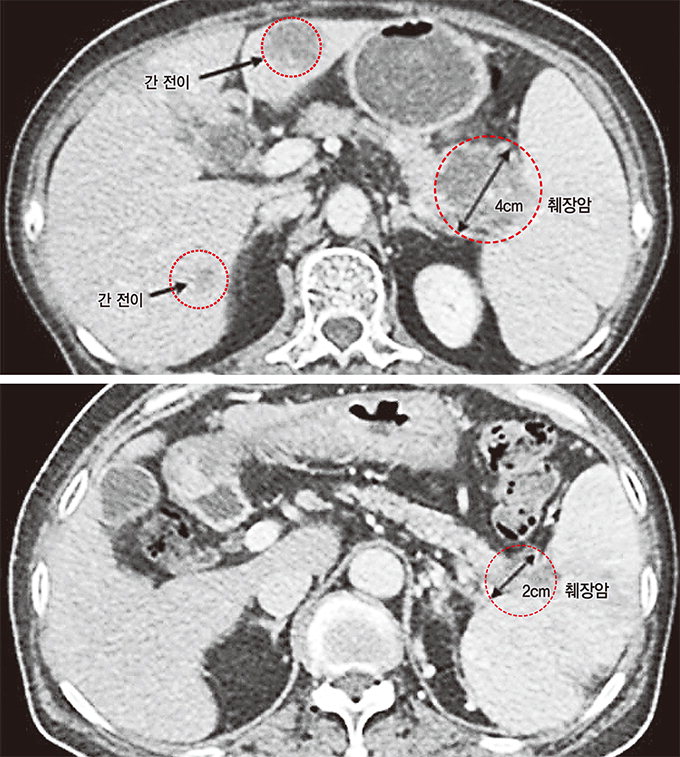

췌장에서 발생하는 종양은 인슐린과 같은 호르몬을 분비하는 내분비세포에서 발생하는 종양의 10%, 소화효소를 분비하는 외분비세포에서 발생하는 종양의 90% 이상으로 구분된다. 내분비 세포에서 유래한 기능성 종양은 매우 드뭅니다. 외분비 세포에서 유래한 선암은 흔히 췌장암이라고 합니다.

췌장암은 췌장의 악성 종양입니다. 다른 암과 마찬가지로 특별한 원인은 없습니다. 노화, 흡연력, 만성 췌장염이 위험인자일 수 있습니다. 특히 췌장암의 발병률은 유전이나 가족력에 의해 크게 증가할 수 있습니다. 가족 중 췌장암 환자가 2명뿐이라고 해도 췌장암 발병 위험은 일반인보다 10배 이상 높다. 이러한 경우는 의학적으로 "가족성 췌장암"으로 알려져 있습니다.